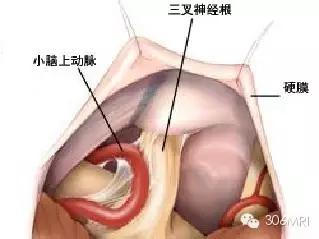

迄今为止,原发性TN 的发病机制仍不完全清楚。三叉神经根脑桥入口处(root entry zone,REZ)的神经血管压迫是目前被广泛接受的病因学说, 1934 年由Dandy 首次提出。该学说认为三叉神经REZ 段受邻近血管的搏动性压迫引起白质纤维脱髓鞘,轴突裸露退变,彼此紧密排列,继而产生异位的自发性神经冲动并传导至邻近神经纤维,最终引起面部疼痛感(图1)。既往研究发现,TN病人的受累神经根病理学表现包括间质性神经炎、神经纤维脱髓鞘以及神经轴索硬化等。在引起TN 的责任血管中,以动脉多见,小脑上动脉是最常见的责任血管,其次为小脑前下动脉、小脑后下动脉、椎基底动脉以及迷路动脉,岩静脉、桥横静脉等,其中静脉压迫仅占TN病因的10%左右。

图1 小脑上动脉压迫三叉神经根示意图